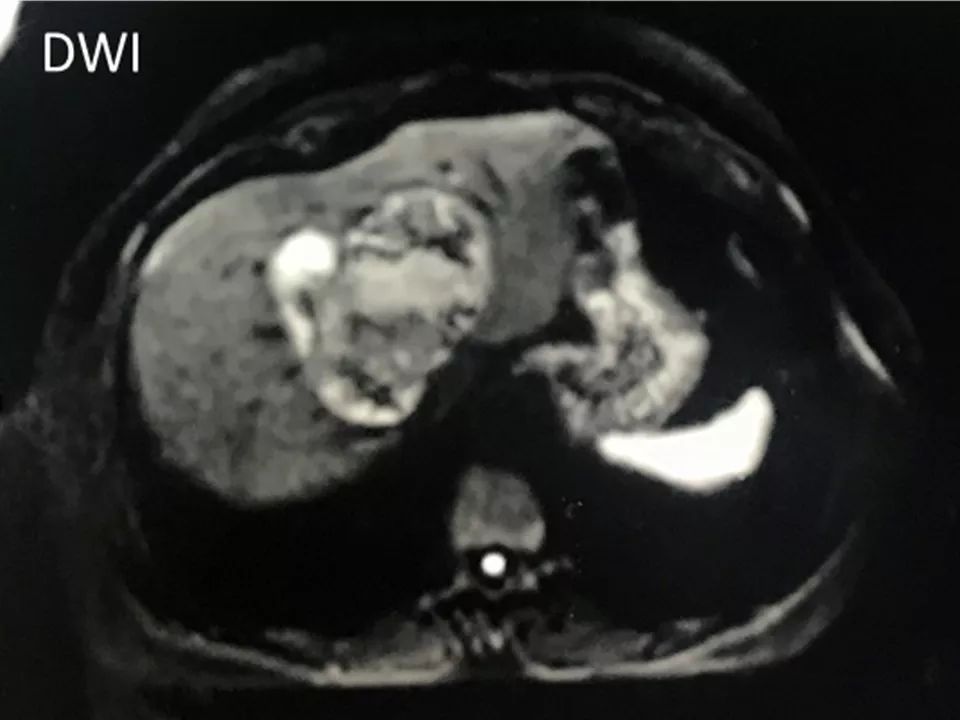

MRI表现:

肝内单发占位灶,累及肝左右叶及尾叶。T1WI示病灶以低信号为主,边缘多枚等信号结节,正反相位未见明显脂肪成份;T2WI示病灶以粘液成份为主呈高信号,边缘多枚稍高信号结节(相对肝实质),DWI呈不均匀等高信号,ADC图以高信号为主。动脉期病灶边缘均匀强化,壁结节显著强化,门脉期边缘仍持续强化,边缘光滑,壁结节呈相对等低信号。MRCP示胆管扩张,病灶与胆管相通。